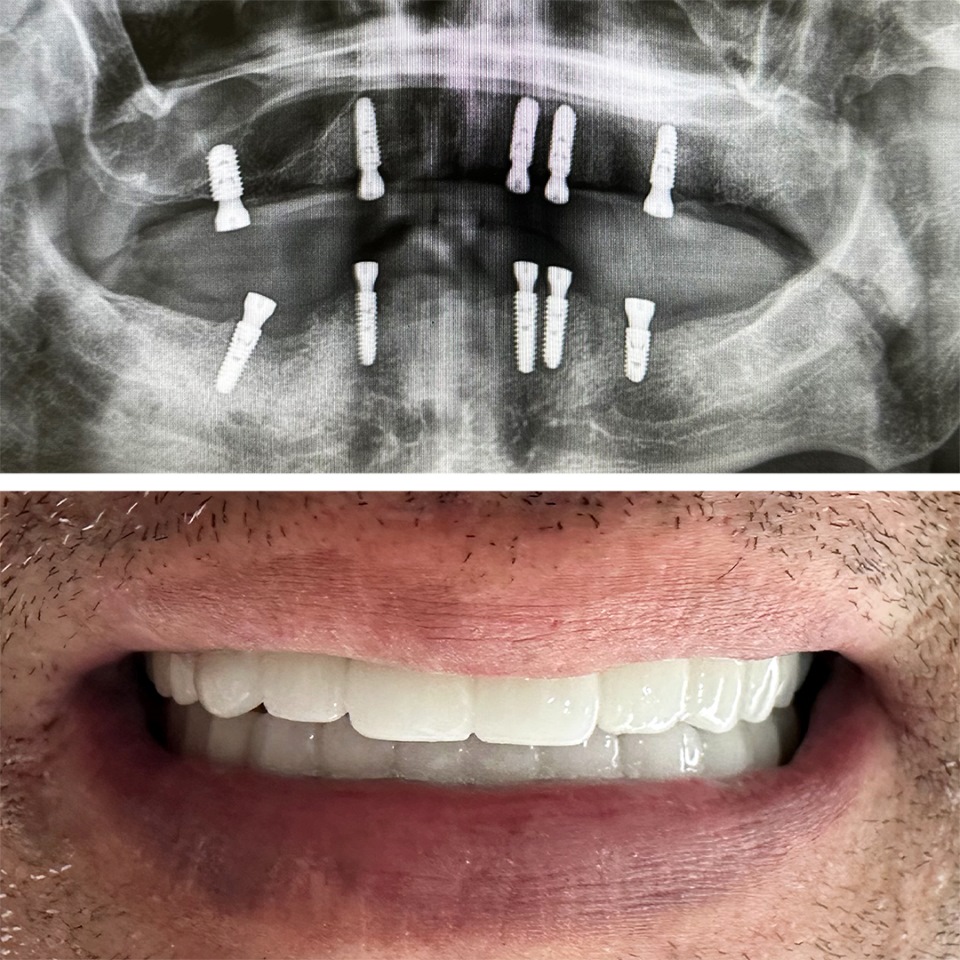

Smile Dental Clinic Turkey Gallery

Our Gallery and Happy Patients

Let’s make a change and put a perfect smile on your face with our dental clinic in Antalya/TURKEY.